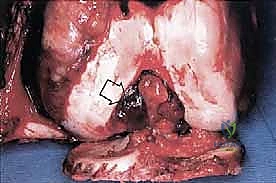

المرحلة الأولى: استئصال الورم (Resection)

يتم فتح الجلد والأنسجة بعناية فائقة. التحدي الأكبر هنا هو فصل الورم عن الأوعية الدموية والأعصاب الرئيسية المغذية للطرف. يستخدم الدكتور هطيف تقنيات الجراحة الميكروسكوبية لضمان سلامة هذه الهياكل الحيوية، مما يحافظ على حيوية الطرف وحركته.

المرحلة الثانية: إعادة البناء العظمي (Skeletal Reconstruction)

بعد إزالة جزء من العظم (أو المفصل بأكمله)، يجب سد الفجوة. تتعدد الخيارات التقنية التي يوفرها الدكتور هطيف في صنعاء:

يتم تقييم مدى استجابة الورم للعلاج الكيميائي (Tumor Necrosis Rate) بعد الاستئصال، وهو مؤشر قوي لفرص الشفاء التام.